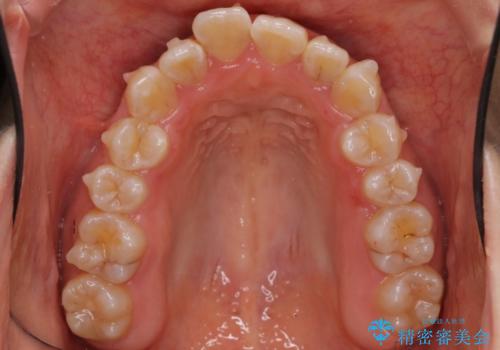

上下の前歯のがたつき 歯を抜かずに矯正

- 上下の前歯のがたつきを主訴に来院。

歯を抜かずに前歯を揃えています。

奥歯を後ろに下げたりなどはしていません。

奥歯を外に広げ、前歯中心に歯を少し削っていますが、健康には問題ない範囲で行なっています。